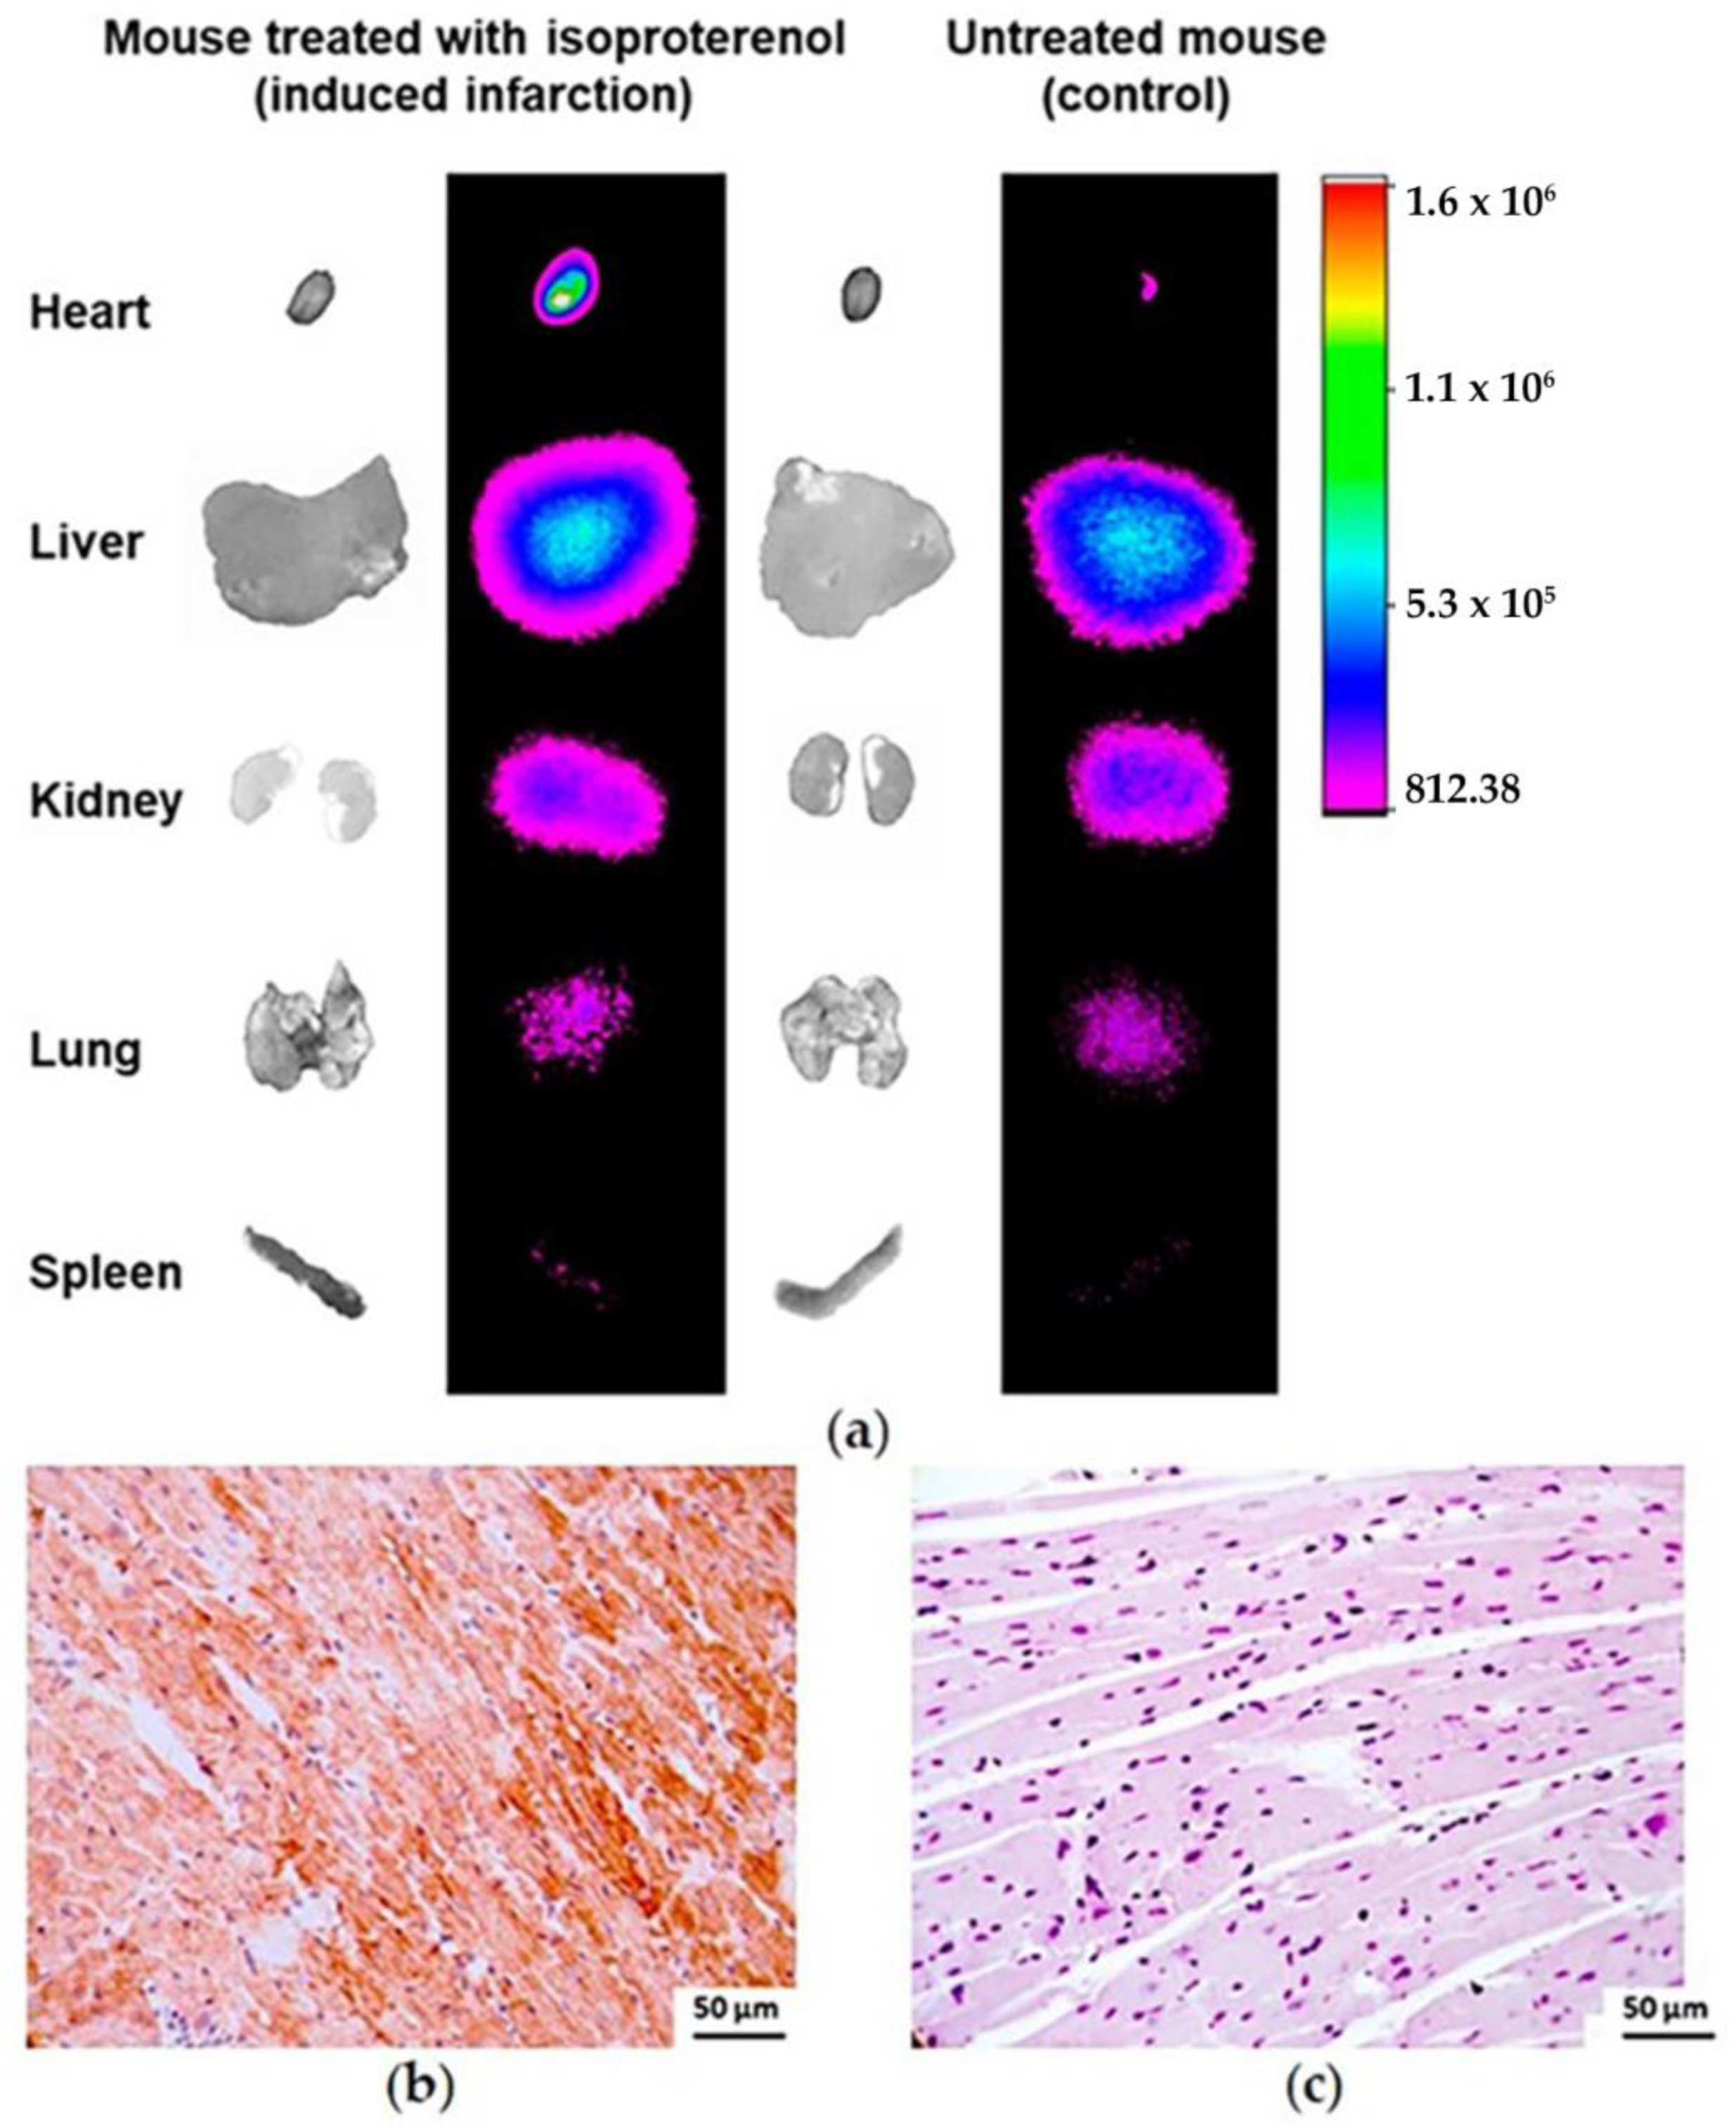

3.4.4. Infarcted Mouse Model Ex Vivo Imaging